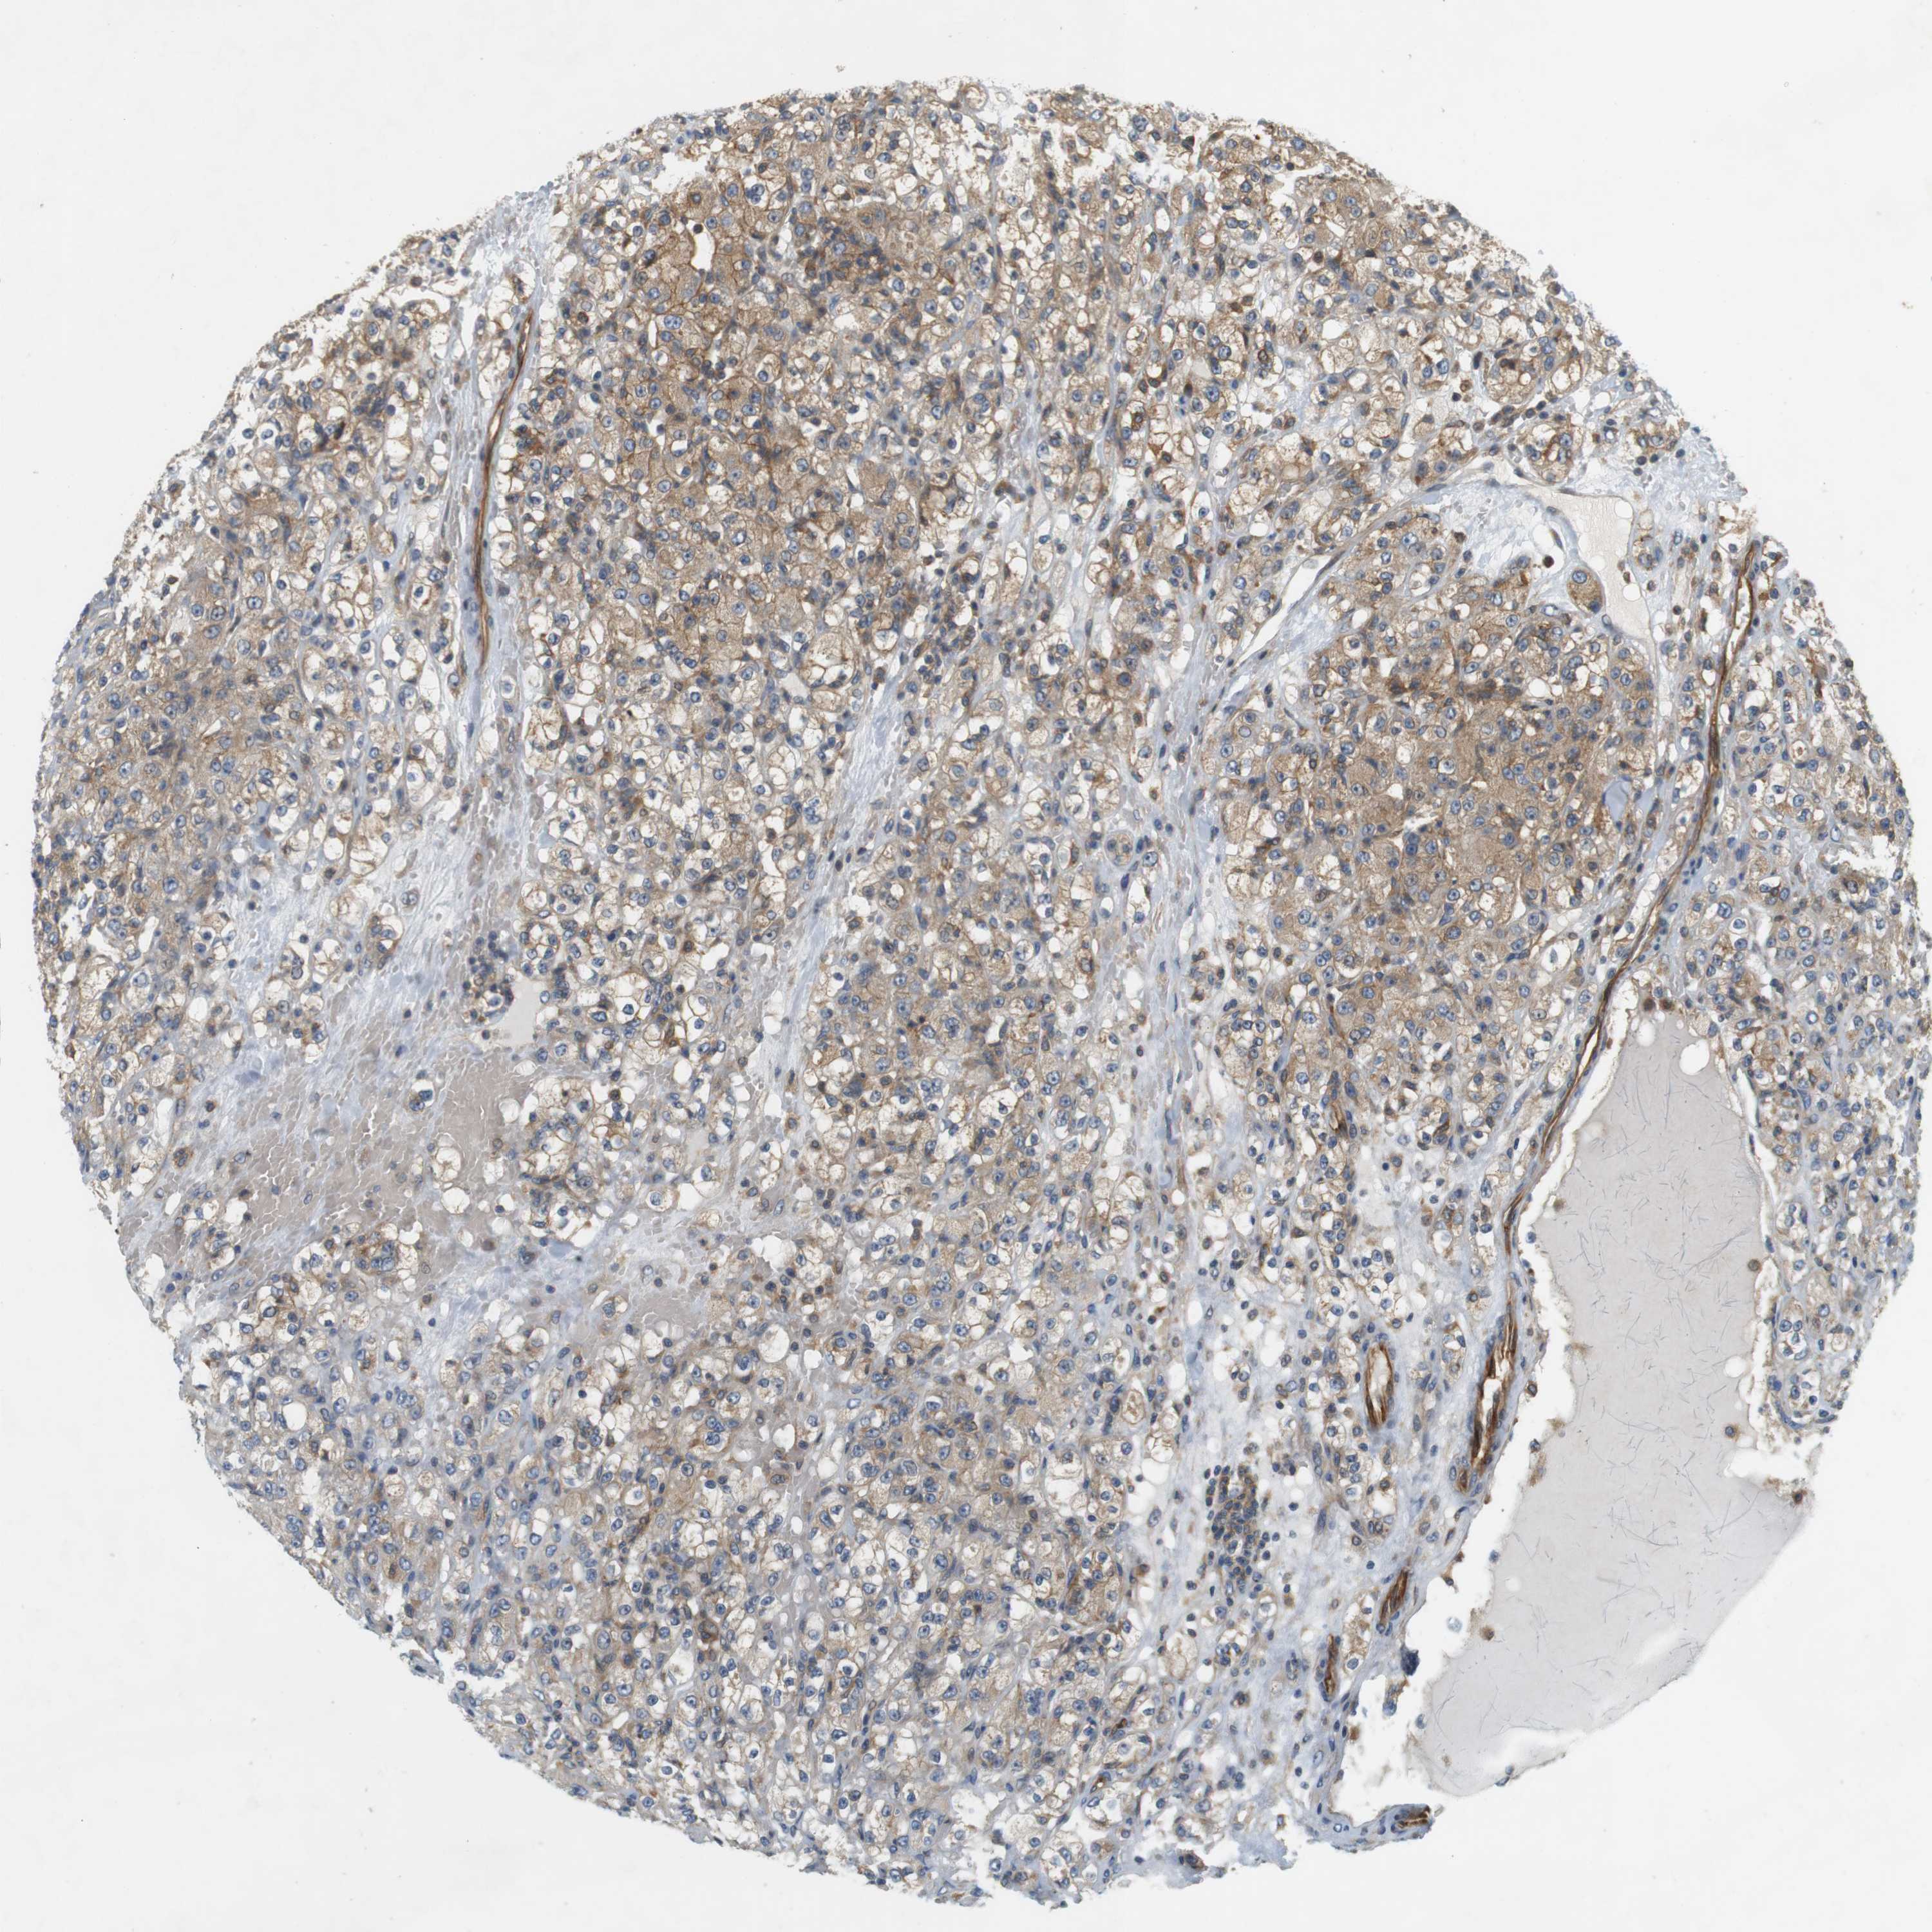

KIDNEY RENAL PAPILLARY CELL CARCINOMA (TCGA) - Interactive survival scatter ploti

The Survival Scatter plot shows the clinical status (i.e. dead or alive) for all individuals in the patient cohort, based on the same data that underlies the corresponding Kaplan-Meier plots. Patients that are alive at last time for follow-up are shown in blue and patients who have died during the study are shown in red.

The x-axis shows the expression levels (FPKM) of the investigated gene in the tumor tissue at the time of diagnosis. The y-axis shows the follow-up time after diagnosis (years). Both axes are complimented with kernel density curves demonstrating the data density over the axes. The top density plot shows the expression levels (FPKM) distribution among dead (red) and alive patients (blue). The right density plot shows the data density of the survived years of dead patients with high and low expression levels respectively, stratified using the cutoff indicated by the vertical dashed line through the Survival Scatter plot. This cutoff is automatically defined based on the FPKM cutoff that minimizes the p-score. The cutoff can be changed by dragging the vertical line or by entering a cutoff value in the square labeled "Current cut-off".

Under the Survival Scatter plot the p-score landscape (black curve; left axis) is shown together with dead median separation (red curve; right axis). Dead median separation is the difference in median mRNA expression between patients who have died with high and low expression, respectively. It is calculated as follows: median FPKM expression of dead patients with high expression - median FPKM expression of dead patients with low expression. This is intended to aid the user in visually exploring custom cutoffs and the associated p-scores and dead median separation.

Individual patient data is displayed and can be filtered by clicking on one or more of the category buttons on the top of the page. Categories describing expression level and patient information include: high, low, alive, dead, female, male and tumor stages. The scale of the x-axis can be toggled between linear and log-scale by clicking on the "x log" button. Mouse-over function shows TCGA ID, patient information and mRNA expression (FPKM) for each patient.

& Survival analysisi

Kaplan-Meier plots summarize results from analysis of correlation between mRNA expression level and patient survival. Patients were divided based on level of expression into one of the two groups "low" (under cut off) or "high" (over cut off). X-axis shows time for survival (years) and y-axis shows the probability of survival, where 1.0 corresponds to 100 percent.

SH3GLB1 is not prognostic in Kidney Renal Papillary Cell Carcinoma (TCGA)